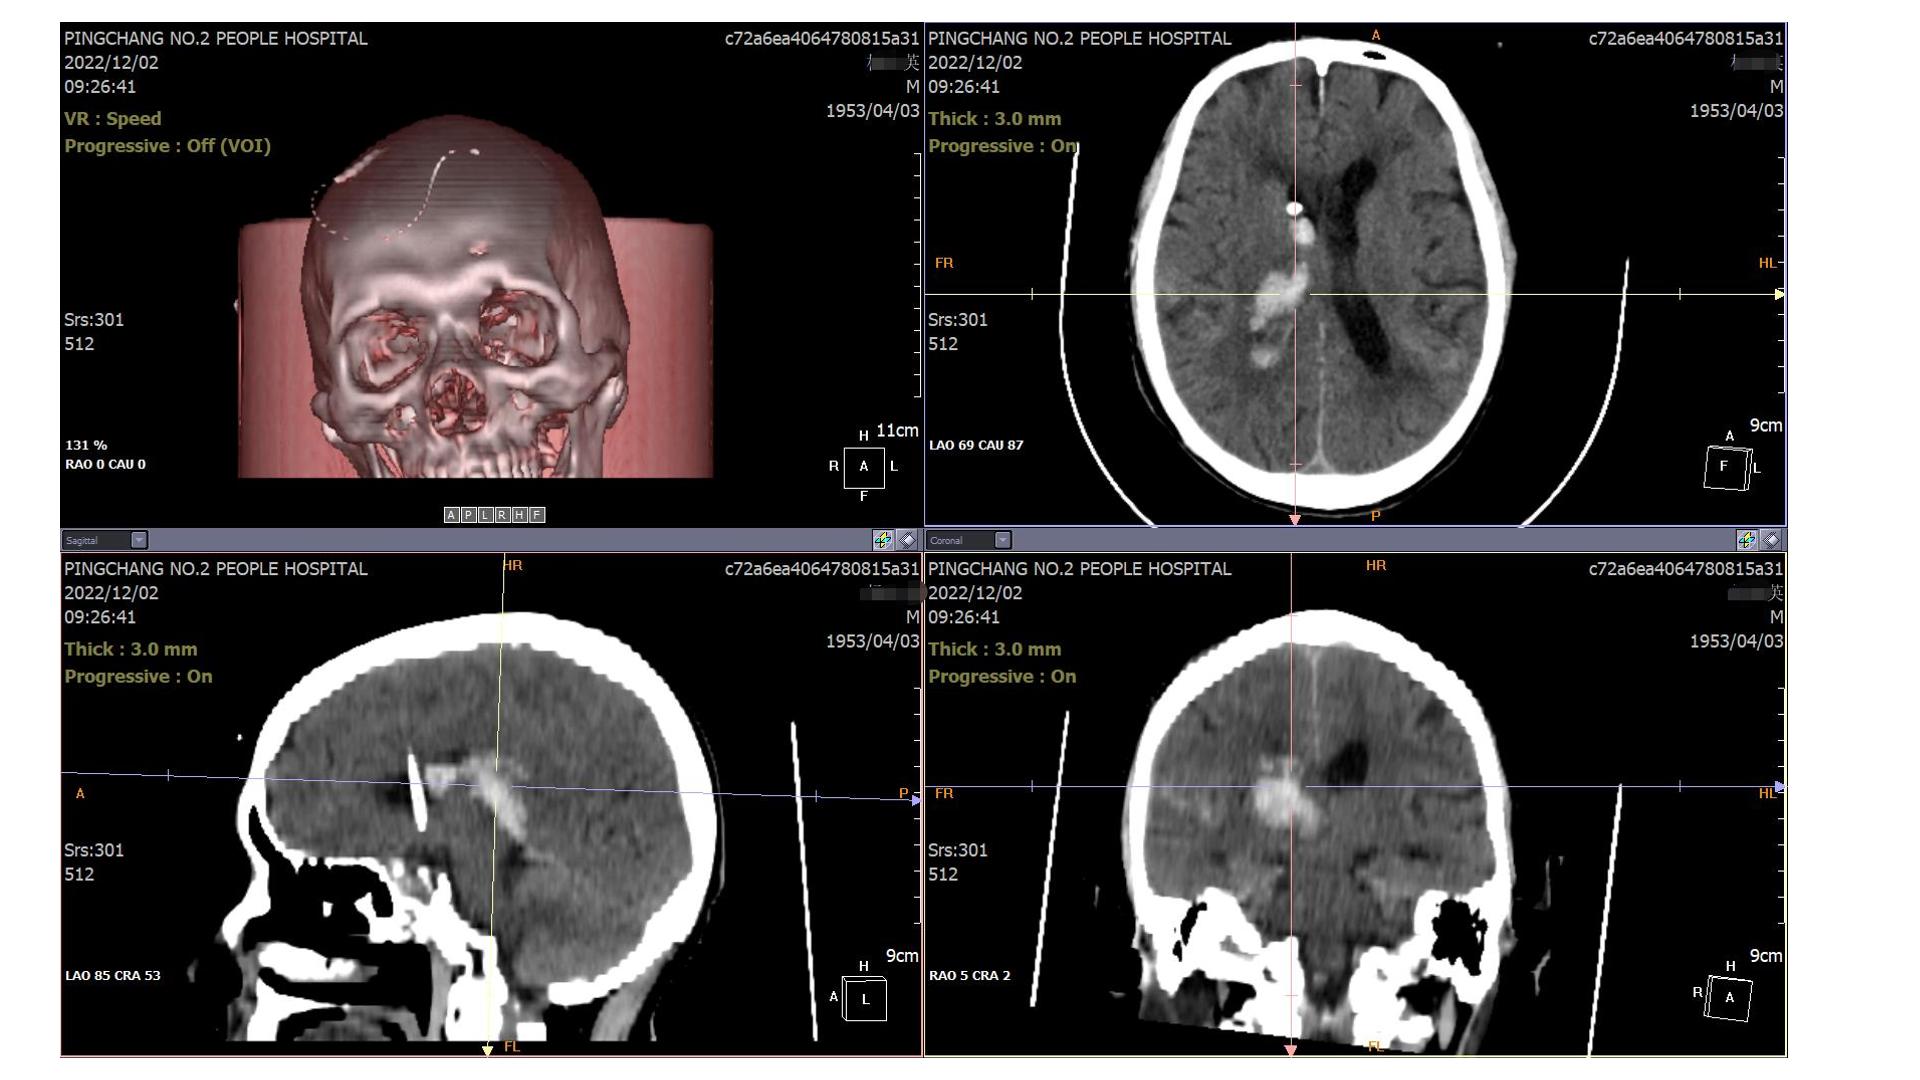

2022.12.02复查(EVD术后),无新增异常,予以局部使用尿激酶